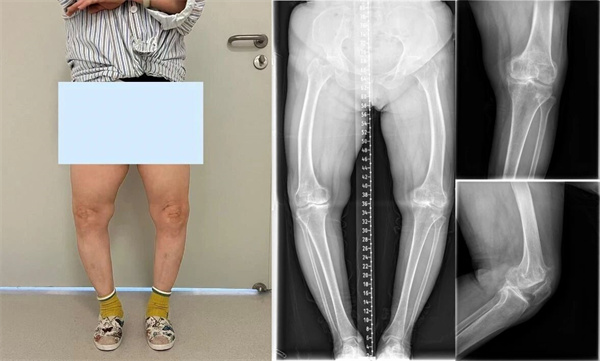

▲术前检查:双膝重度内翻变形,X线片双膝重度骨关节炎改变

入院完善相关检查后,运动医学与关节外科(骨二科)特聘专家邢更彦详细查看了患者情况。患者双膝呈重度内翻畸形,左侧为重,屈伸活动严重受限,膝内侧及髌股关节间隙明显狭窄,且左侧膝外侧副韧带存在松弛。邢更彦与患者及家属进行了深入沟通后表示,患者因重度膝内翻继发骨性关节炎,膝关节疼痛与活动受限已严重影响其日常生活。若采用传统膝关节周围截骨矫形,虽可恢复下肢负重力线,但患者年龄偏大且关节退变严重,无法确保有效缓解疼痛。对于如此严重的畸形合并侧副韧带松弛的情况,常规的初次膝关节置换手术亦不适用。经综合评估,团队最终为患者制定LCCK膝关节置换术手术方案。

▲术后:X线见左下肢力线恢复正常,患者早期康复锻炼